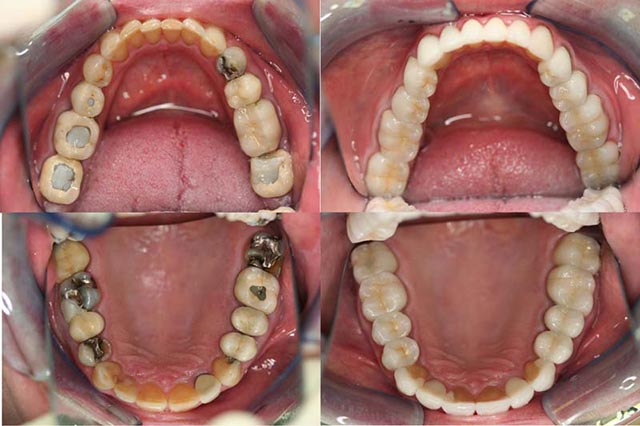

Before And After Bridges and Crowns Treatment